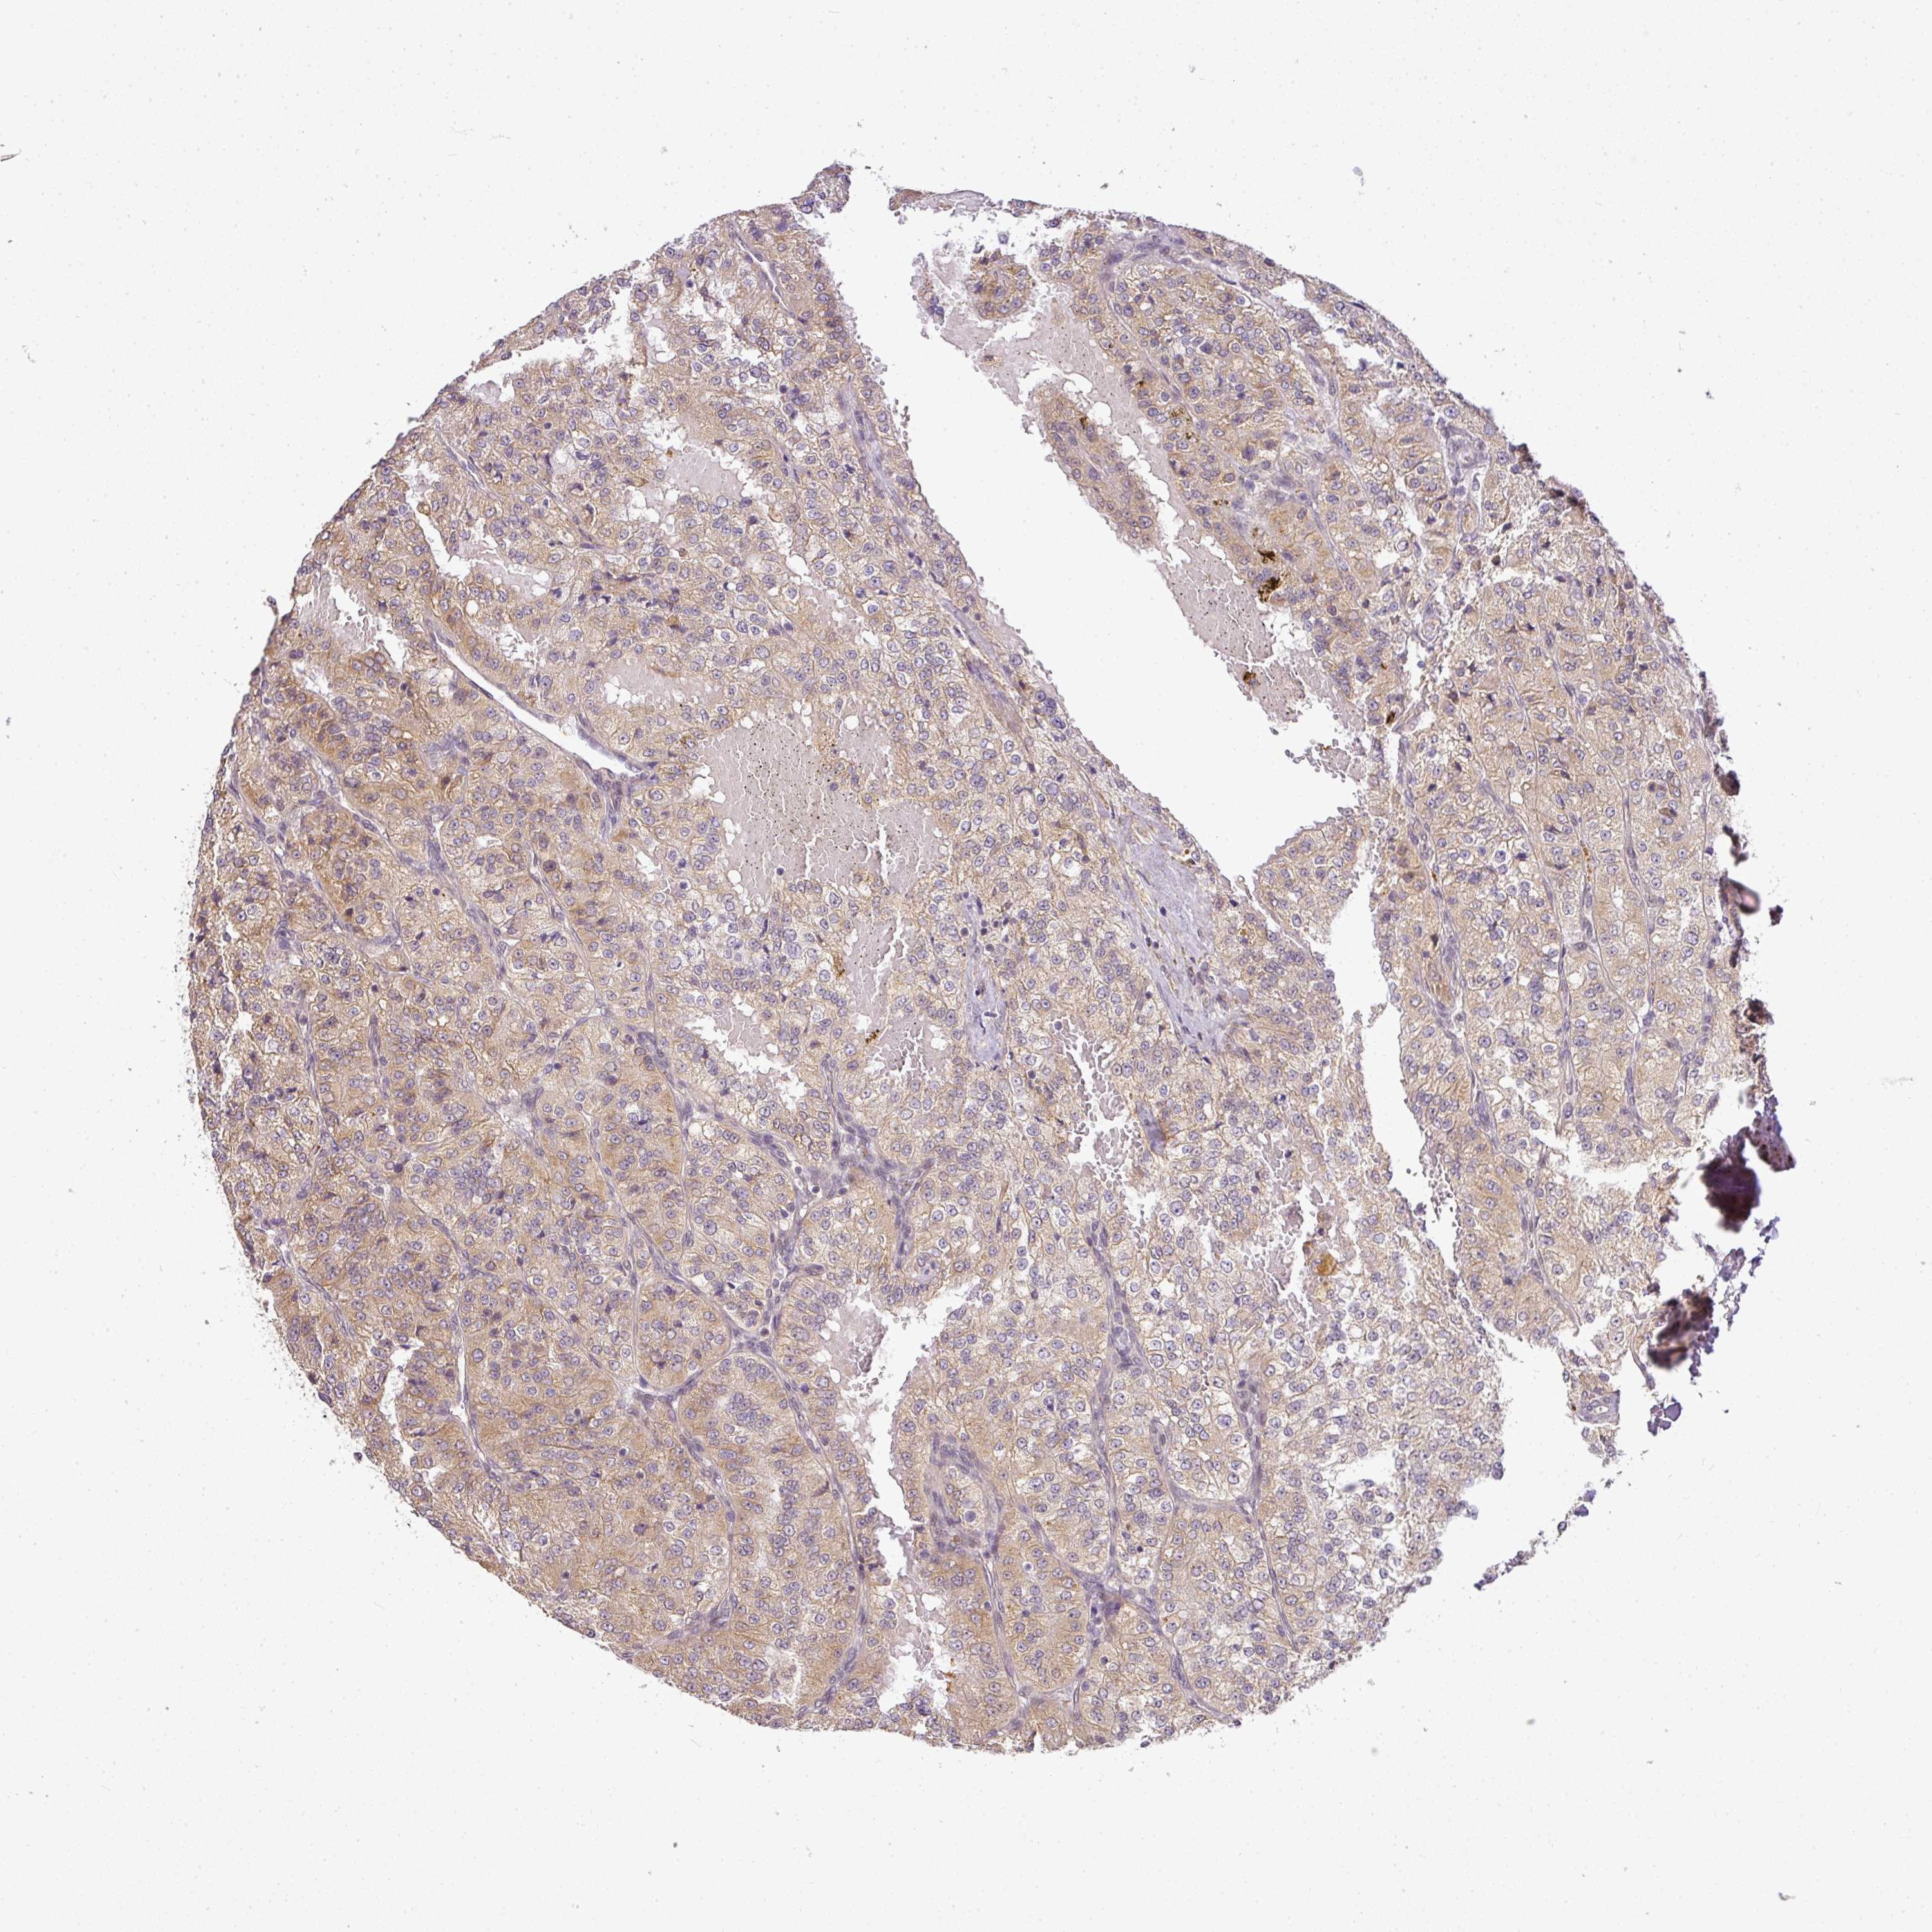

KIDNEY RENAL CLEAR CELL CARCINOMA (VALIDATION) - Interactive survival scatter ploti

The Survival Scatter plot shows the clinical status (i.e. dead or alive) for all individuals in the patient cohort, based on the same data that underlies the corresponding Kaplan-Meier plots. Patients that are alive at last time for follow-up are shown in blue and patients who have died during the study are shown in red.

The x-axis shows the expression levels (FPKM) of the investigated gene in the tumor tissue at the time of diagnosis. The y-axis shows the follow-up time after diagnosis (years). Both axes are complimented with kernel density curves demonstrating the data density over the axes. The top density plot shows the expression levels (FPKM) distribution among dead (red) and alive patients (blue). The right density plot shows the data density of the survived years of dead patients with high and low expression levels respectively, stratified using the cutoff indicated by the vertical dashed line through the Survival Scatter plot. This cutoff is automatically defined based on the FPKM cutoff that minimizes the p-score. The cutoff can be changed by dragging the vertical line or by entering a cutoff value in the square labeled "Current cut-off".

Under the Survival Scatter plot the p-score landscape (black curve; left axis) is shown together with dead median separation (red curve; right axis). Dead median separation is the difference in median mRNA expression between patients who have died with high and low expression, respectively. It is calculated as follows: median FPKM expression of dead patients with high expression - median FPKM expression of dead patients with low expression. This is intended to aid the user in visually exploring custom cutoffs and the associated p-scores and dead median separation.

Individual patient data is displayed and can be filtered by clicking on one or more of the category buttons on the top of the page. Categories describing expression level and patient information include: high, low, alive, dead, female, male and tumor stages. The scale of the x-axis can be toggled between linear and log-scale by clicking on the "x log" button. Mouse-over function shows TCGA ID, patient information and mRNA expression (FPKM) for each patient.

& Survival analysisi

Kaplan-Meier plots summarize results from analysis of correlation between mRNA expression level and patient survival. Patients were divided based on level of expression into one of the two groups "low" (under cut off) or "high" (over cut off). X-axis shows time for survival (years) and y-axis shows the probability of survival, where 1.0 corresponds to 100 percent.

ENSG00000254706 is not prognostic in Kidney Renal Clear Cell Carcinoma (validation)

TCGA RNA samplesi

RNA-seq data is reported as average FPKM (number Fragments Per Kilobase of exon per Million reads), generated by the The Cancer Genome Atlas (TCGA) .

Normal distribution across the dataset is visualized with box plots, shown as median and 25th and 75th percentiles. Points are displayed as outliers if they are above or below 1.5 times the interquartile range. FPKM values of the individual samples are presented next to the box plot.

Average pTPM 0.4

Number of samples 100